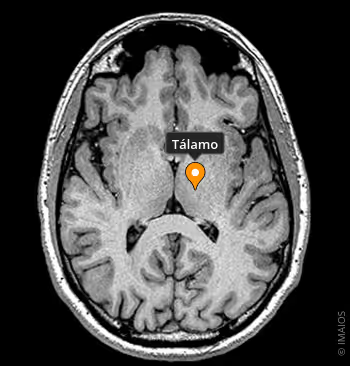

1-TÁLAMO

Vital para a perceção sensorial e consciência. Ela tem a função de produzir a Dopamina, substância neurotransmissor envolvida no circuito de recompensa do Cérebro e mensageira química, essencial para o sistema nervoso.

De especial importância em várias funções corporais, tais como na liberação de satisfação, prazer, humor e controle motor.

Quando temos níveis reduzidos de Dopamina, normalmente entramos em estados de depressão, psicose e esquizofrenia, falta de interesse, podendo levar à doença de Parkinson